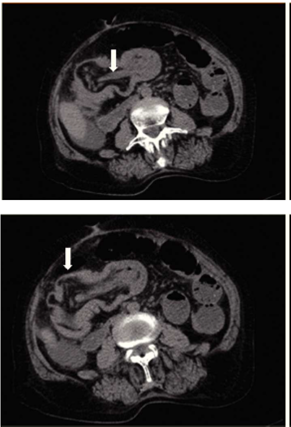

La tomografía computarizada es actualmente la herramienta más confiable para el diagnóstico de los lipomas colónicos; mostrando una tumoración esférica con bordes regulares bien delimitados con densidades de absorción de entre −40 a −120 unidades Hounsfield, compatible con tejido graso.9,12En el caso de la intususcepción intestinal secundaria a lipoma colónico, la tomografía computarizada es el método preferido para el diagnóstico. Reportándose una sensibilidad de 71.4-87.5% y una especificidad del 100% verificada con la cirugía subsecuente.34 A pesar de las herramientas diagnósticas el diagnóstico diferencial con procesos malignos es el principal reto previo al procedimiento quirúrgico.

Se trata de paciente femenino de 77 años de edad, con antecedente de hipertensión arterial sistémica, ingresa a nuestro servicio por presentar cuadro doloroso abdominal intenso de una semana de evolución (fig. 1), acompañado de distensión abdominal náusea y vómito, el cual no remitió con la administración de analgésicos, acudió a valoración por facultativo quien solicitó ultrasonograma (USG) abdominal evidenciando la presencia de un tumor en colon derecho, se ingresó a la paciente por presentar persistencia de la sintomatología. A la exploración física hemodinámicamente estable se encontró abdomen distendido, doloroso a la palpación, superficial, media y profunda en cuadrantes abdominales inferiores y ruidos metálicos a la auscultación, con datos de irritación peritoneal. Paraclínicos con leucocitosis leve únicamente. En el USG abdominal reportó en flanco derecho una imagen ecogénica, redondeada, bien delimitada, con medidas de 41 × 38 × 59 mm en sus ejes mayores, la cual a la aplicación de Doppler color no mostró vascularidad, esta zona es aperistáltica, en relación a conglomerado de asas. No se identifica líquido libre. La TAC abdominal (fig. 2) con imágenes compatibles a oclusión intestinal probablemente secundaria a invaginación intestinal a nivel de ciego y colon ascendente, la cual condicionaba ascitis y neumatosis intestinal leve, además de probable adenoma suprarrenal derecho. Con lo anteriormente mencionado se infiere diagnóstico de invaginación intestinal, por lo cual se programa de urgencia para laparotomía exploradora.